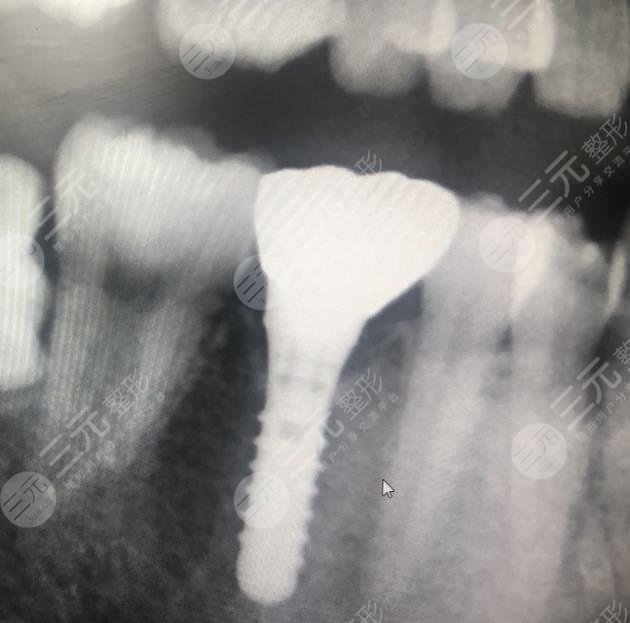

二、成都圣貝口腔醫(yī)院種植牙經(jīng)歷分享

我的牙齒有一顆牙齒壞了很久了,所以我一直想要修復,但是我又不想拔掉,所以就很糾結(jié),不知道怎么樣的方式才能夠改良,經(jīng)過朋友的一番介紹說,我還是選擇到口腔醫(yī)院里面檢查一番,然后再決定具體的緩解方法。在和口腔醫(yī)院的醫(yī)生溝通之后,他說像我這種方情況必須要把原有的壞牙拔掉之后換新的牙齒,不會有口腔造成疾病的情況。

成都圣貝口腔醫(yī)院種植牙經(jīng)歷分享

在聽了醫(yī)生的介紹之后,我決定選擇使用這種方法,沒想到這種方法確實GET了不錯的目的,現(xiàn)在我種植牙齒之后已經(jīng)有快兩年的時間了,沒有出現(xiàn)任何的副作用,平時也沒有出現(xiàn)牙齒疼痛的現(xiàn)象。